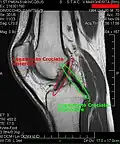

Ressonância magnética (RM) de um joelho. -